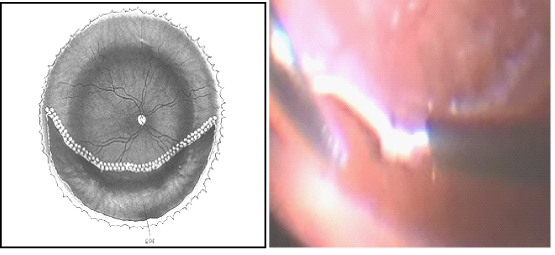

Management of these cases depended, in our study, on whether a PVR was present or not (Figure 2).

Figure 2: Management options for cases of recurrent retinal detachment under SO.

Hydraulic reattachment of the retina: (Figure 3) Silicone oil fluid exchange must be done slowly with:

1. Flute needle put in the retinal break in the fluid meniscus.

2. Observe the fluid–silicone oil interface over the flute needle shaft as it goes down towards the retina.

3. Observe the arterial pulsations over disc to avoid excessive increase in IOP & SO passing under the retina if residual traction was present.

Figure 3 Hydraulic reattachment of the retina.

This technique was used as a theraputic measure in case of failure of face down position, either due to patient non compliance (2 cases) or viscid sub-retinal fluid (1 case). The technique was also useful to diagnose intrinsic contraction of the retina where the retina remained elevated and in some cases the retinal break enlarged gradually as the silicone oil was injected. In these cases, care must be taken to stop silicone oil injection otherwise it will go under the retina. A retinotomy was done in those 3 cases.